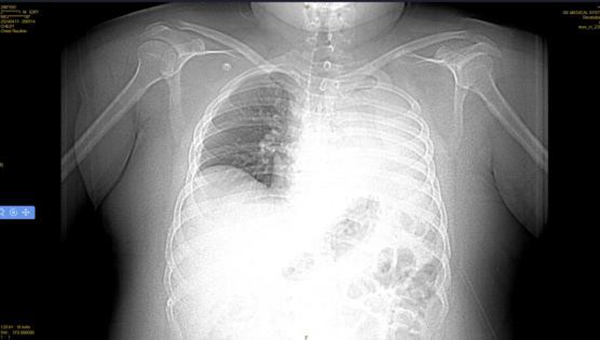

4月14日,王先生因“憋喘伴發(fā)熱咳嗽半月余”到徐州醫(yī)科大學(xué)附屬醫(yī)院急診就診。據(jù)王先生家人介紹,患者半個(gè)多月來,憋喘不斷加重,先后在徐州市多家醫(yī)院就診,考慮左肺不張伴感染,但通過積極抗感染治療,憋喘無改善并逐漸加重,同時(shí)出現(xiàn)發(fā)熱癥狀,體溫最高近39攝氏度。徐醫(yī)附院呼吸與危重癥醫(yī)學(xué)科何軍主任會(huì)診后,考慮患者智力異常,進(jìn)食方式特殊,不排除誤吸的情況,閱片后發(fā)現(xiàn)左主支氣管內(nèi)存在異物可能,需行氣管鏡檢查進(jìn)一步明確肺內(nèi)情況。考慮患者一般情況差,存在I型呼吸衰竭,肺部感染重等情況,于是將其收治在呼吸重癥監(jiān)護(hù)室(RICU)。

后續(xù)給與積極抗感染等治療,復(fù)查胸片示左肺不張改善,體溫正常,炎癥指標(biāo)下降,再次復(fù)查氣管鏡下可見痰量較前明顯減少,總體病情好轉(zhuǎn),4月23日轉(zhuǎn)到普通病房繼續(xù)治療;颊呒覍俦硎荆氜D(zhuǎn)三家醫(yī)院就醫(yī),還是徐醫(yī)附院最值得信任,對(duì)呼吸ICU全體醫(yī)護(hù)人員表達(dá)了敬意和衷心感謝。